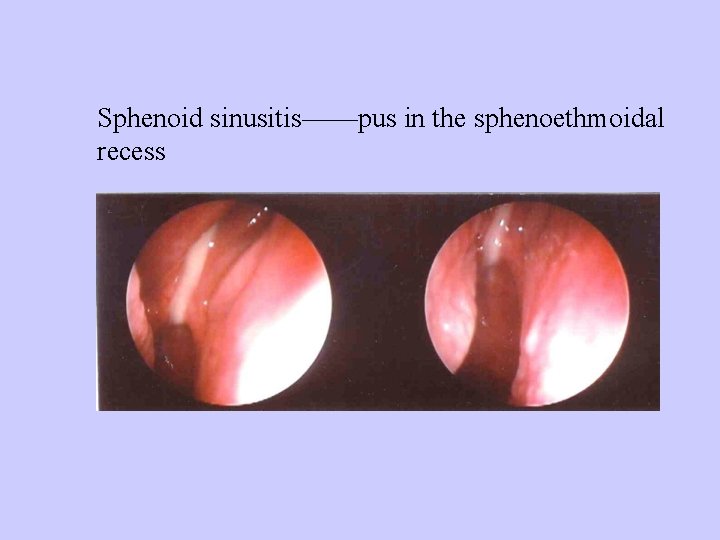

Sphenoid sinusitis——pus in the sphenoethmoidal recess